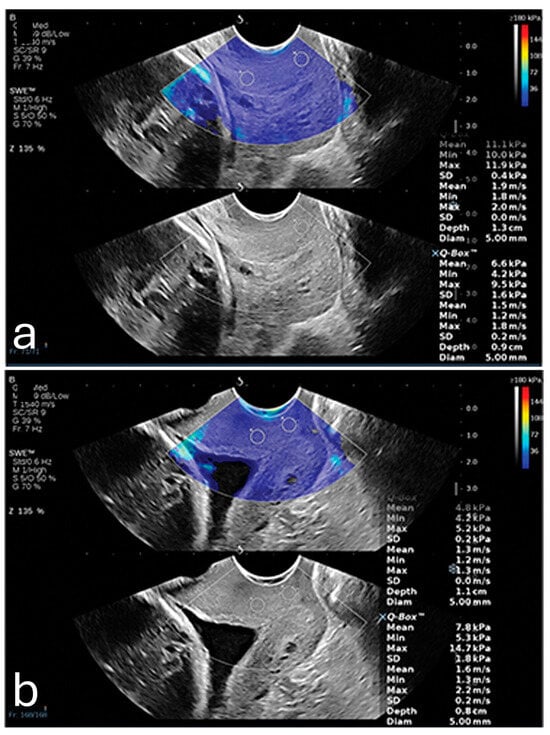

Furthermore, a 2024 study demonstrated that SWE could precisely measure tissue elasticity at specific cervical points, such as the inner and outer cervical os, yielding predictive values higher than cervical length alone []. When incorporated into a multifactorial model that included cervical length and pregnancy-related comorbidities, SWE achieved an AUC of 0.892, with a sensitivity of 86.7% and specificity of 79.2%. It also showed that SWE values were lower in PTB (8.76 kPa ± 3.04 kPa) in comparison to full-term pregnancies (14.95 kPa ± 8.21 kPa). These findings were most consistent when samples were taken from the anterior or posterior lip of the internal os, as illustrated in Figure 1. This combined approach shows promise for developing a more comprehensive PTB risk model that integrates both elastographic data and clinical factors [].

Figure 1. (a) Shear wave elastography image from a 26-year-old woman at 35 weeks gestation, showing high stiffness (11.1 kPa) in the anterior internal os; this patient delivered naturally at 38 + 4 weeks. (b) Shear wave elastography image from a 31-year-old woman at 34 weeks gestation, showing reduced stiffness (4.8 kPa) in the anterior internal os; this patient experienced preterm birth at 35 + 2 weeks due to premature rupture of membranes. Image adapted from Smith et al. [] under a Creative Commons Attribution 4.0 International License. Changes were made to resize and adjust the images.